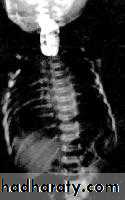

LEFT: Dilated esophagus (arrows) appears as long, well-defined structure paralleling heart RIGHT: Dilated esophagus usually deviates to right. Narrowing (arrow) at hiatus.

LEFT: CT shows dilated esophagus (arrow) that led to esophagram.RIGHT: Esophagram shows narrowing (arrow) at level of hiatus.